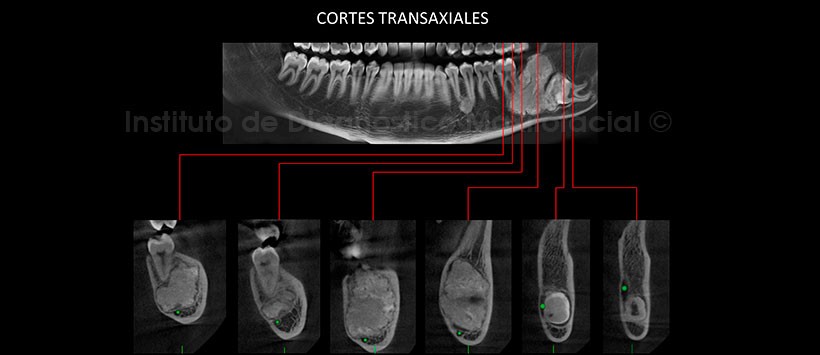

En los cortes axiales de maxilar inferior, pudimos observar el aumento de tamaño de la tabla ósea lingual y vestibular, siendo esta ultima la de mayor predominio (Figura 2). Así mismo en los cortes transaxiales y tangenciales podemos observar la estrecha relación de esta lesión con los ápices de la pieza 37, también se aprecia el adelgazamiento de a cortical lingual a causa de esta lesión y el desplazamiento hacia caudal del conducto dentario inferior. (Figura 3 y Figura 4)